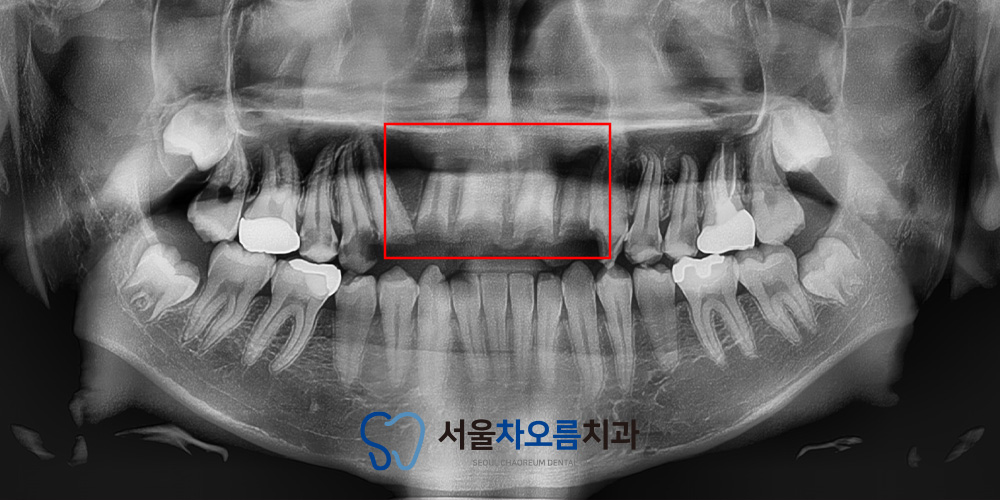

자세한 확인을 위해

파노라마를 촬영해보았습니다.

치아의 머리 부분이 전체적으로

파절이 되어 뿌리만 남아있는

상황이였습니다.

치아를 살리기에는 구조적으로

어려움이 있었기 때문에

병점치과 365서울차오름에서는

발치 후 임플란트 식립을 통해

안정적이고 기능적인 회복을 위한

치료 계획을 수립하였습니다.